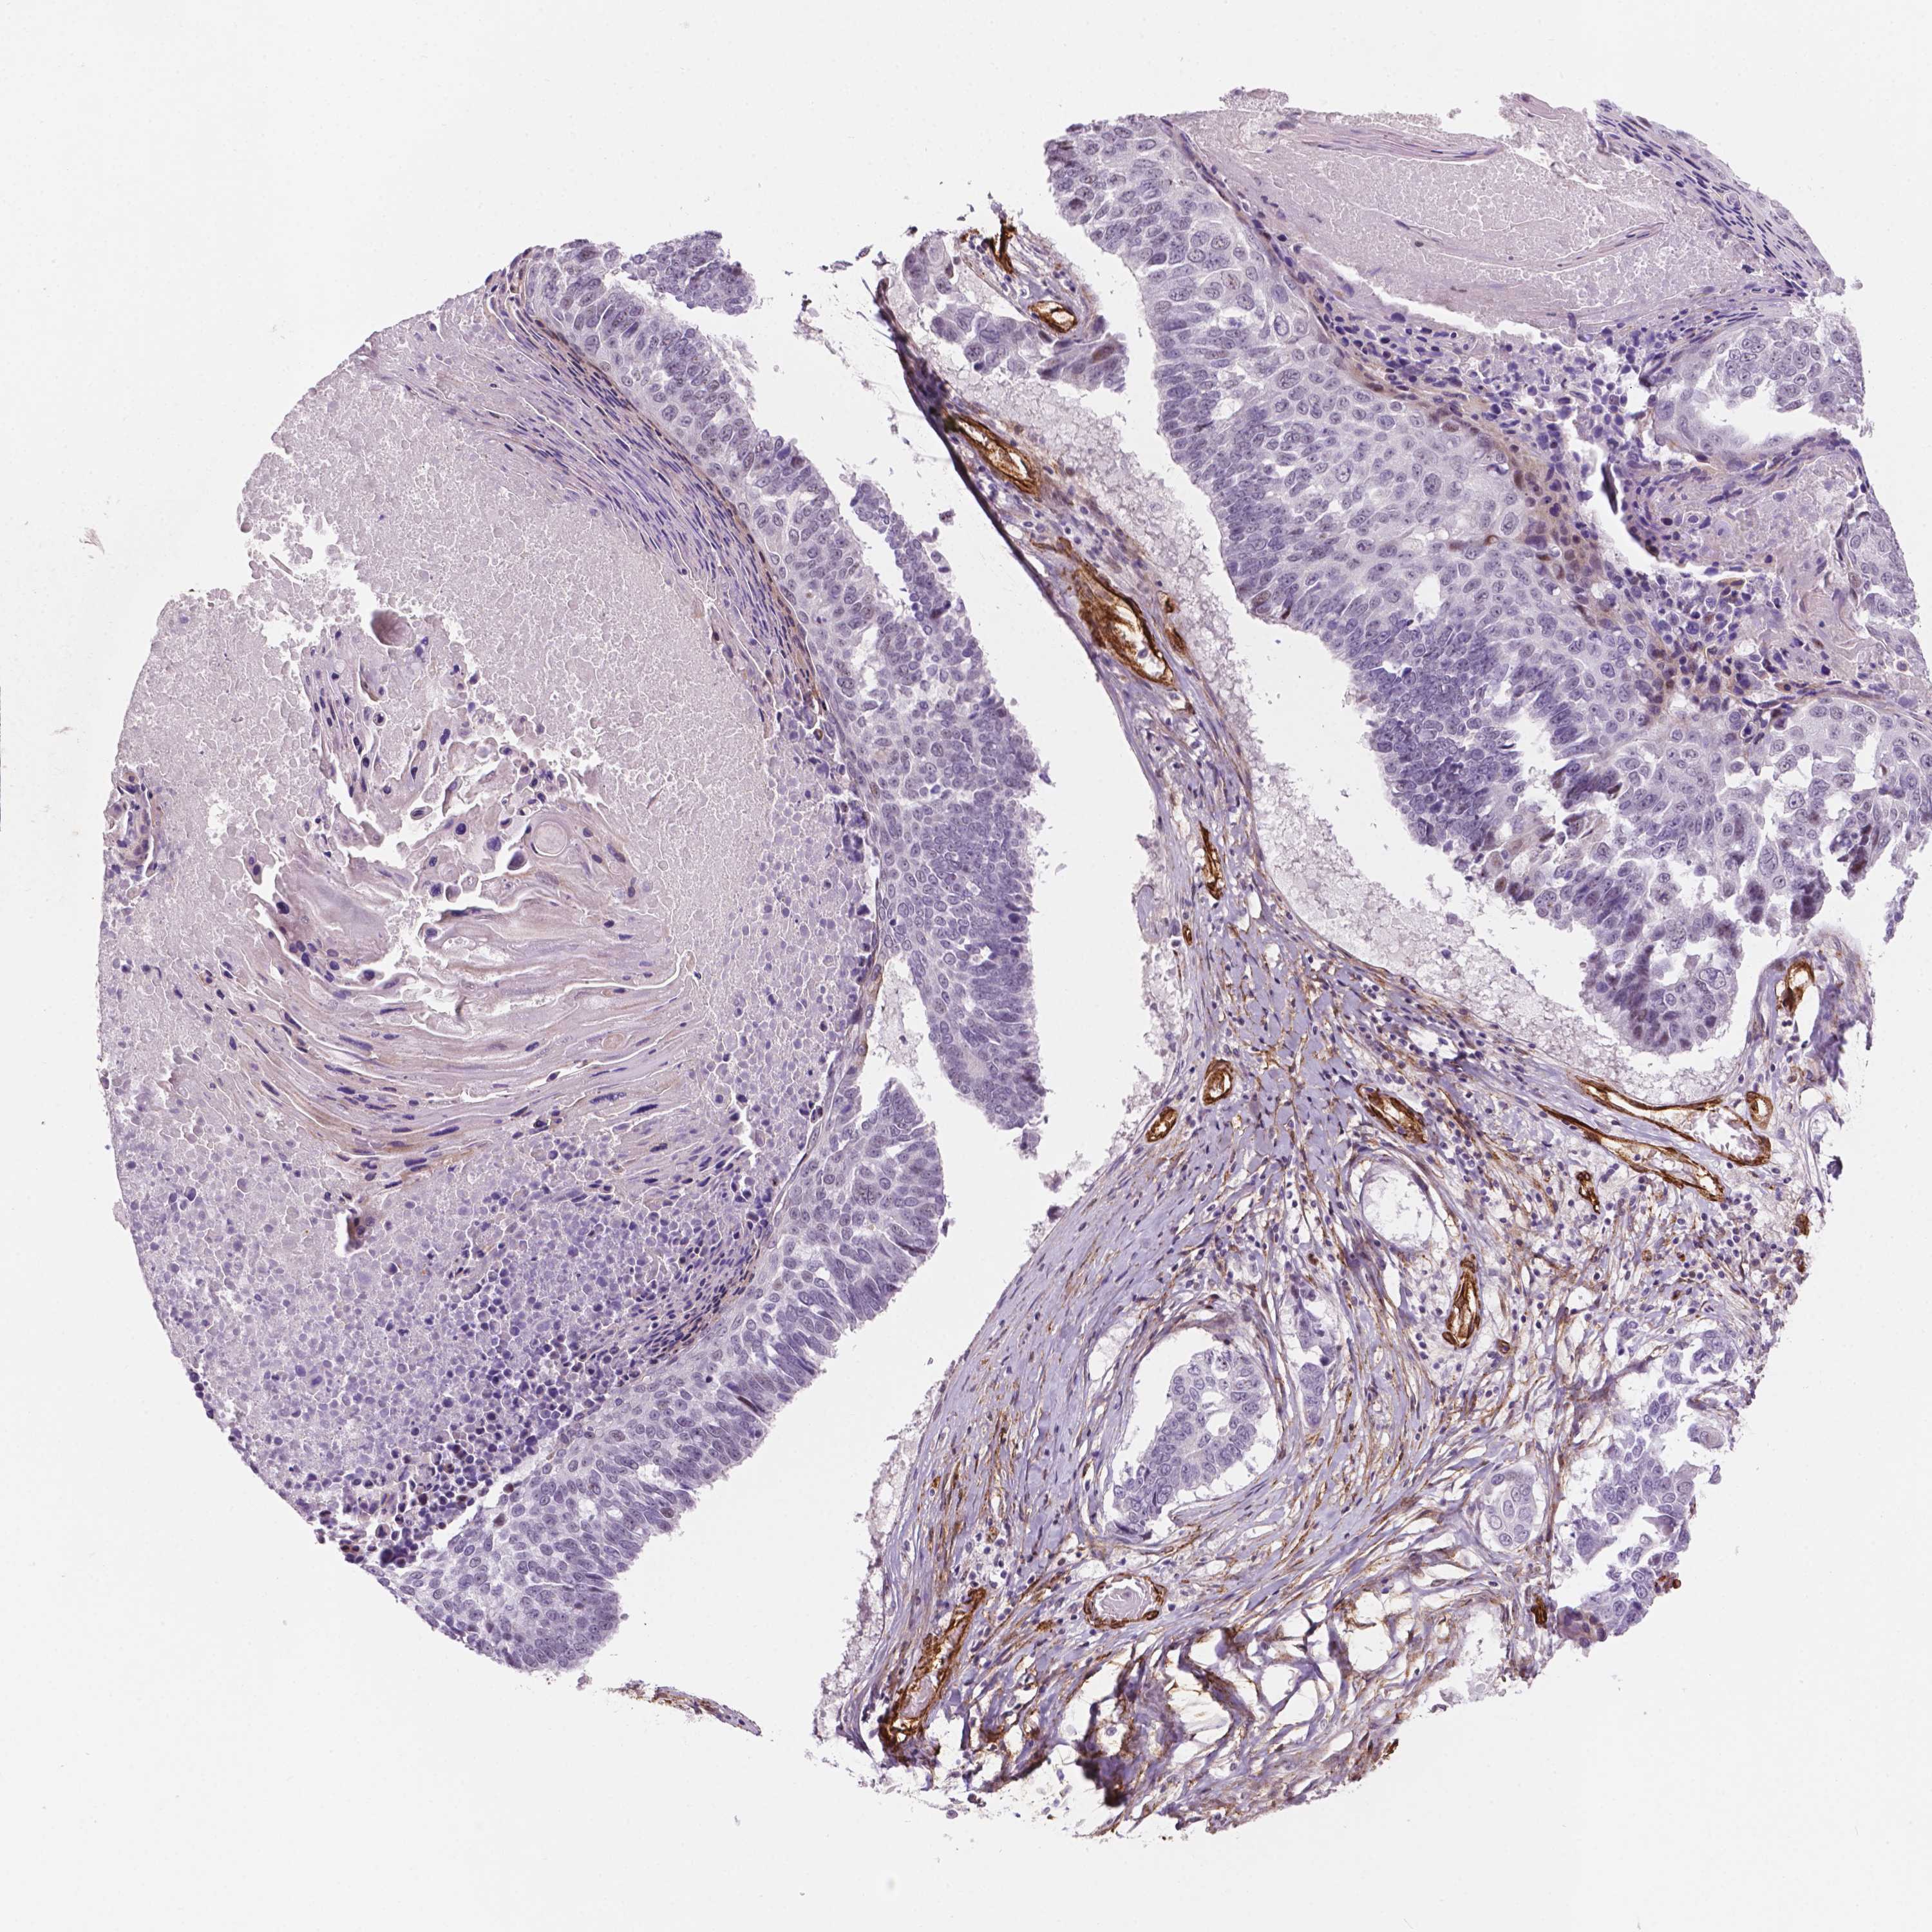

LUNG SQUAMOUS CELL CARCINOMA (TCGA) - Interactive survival scatter ploti

The Survival Scatter plot shows the clinical status (i.e. dead or alive) for all individuals in the patient cohort, based on the same data that underlies the corresponding Kaplan-Meier plots. Patients that are alive at last time for follow-up are shown in blue and patients who have died during the study are shown in red.

The x-axis shows the expression levels (FPKM) of the investigated gene in the tumor tissue at the time of diagnosis. The y-axis shows the follow-up time after diagnosis (years). Both axes are complimented with kernel density curves demonstrating the data density over the axes. The top density plot shows the expression levels (FPKM) distribution among dead (red) and alive patients (blue). The right density plot shows the data density of the survived years of dead patients with high and low expression levels respectively, stratified using the cutoff indicated by the vertical dashed line through the Survival Scatter plot. This cutoff is automatically defined based on the FPKM cutoff that minimizes the p-score. The cutoff can be changed by dragging the vertical line or by entering a cutoff value in the square labeled "Current cut-off".

Under the Survival Scatter plot the p-score landscape (black curve; left axis) is shown together with dead median separation (red curve; right axis). Dead median separation is the difference in median mRNA expression between patients who have died with high and low expression, respectively. It is calculated as follows: median FPKM expression of dead patients with high expression - median FPKM expression of dead patients with low expression. This is intended to aid the user in visually exploring custom cutoffs and the associated p-scores and dead median separation.

Individual patient data is displayed and can be filtered by clicking on one or more of the category buttons on the top of the page. Categories describing expression level and patient information include: high, low, alive, dead, female, male and tumor stages. The scale of the x-axis can be toggled between linear and log-scale by clicking on the "x log" button. Mouse-over function shows TCGA ID, patient information and mRNA expression (FPKM) for each patient.

& Survival analysisi

Kaplan-Meier plots summarize results from analysis of correlation between mRNA expression level and patient survival. Patients were divided based on level of expression into one of the two groups "low" (under cut off) or "high" (over cut off). X-axis shows time for survival (years) and y-axis shows the probability of survival, where 1.0 corresponds to 100 percent.

EGFL8 is not prognostic in Lung Squamous Cell Carcinoma (TCGA)

TCGA RNA samplesi

RNA-seq data is reported as average FPKM (number Fragments Per Kilobase of exon per Million reads), generated by the The Cancer Genome Atlas (TCGA) .

Normal distribution across the dataset is visualized with box plots, shown as median and 25th and 75th percentiles. Points are displayed as outliers if they are above or below 1.5 times the interquartile range. FPKM values of the individual samples are presented next to the box plot.

Average pTPM 0.4

Number of samples 489